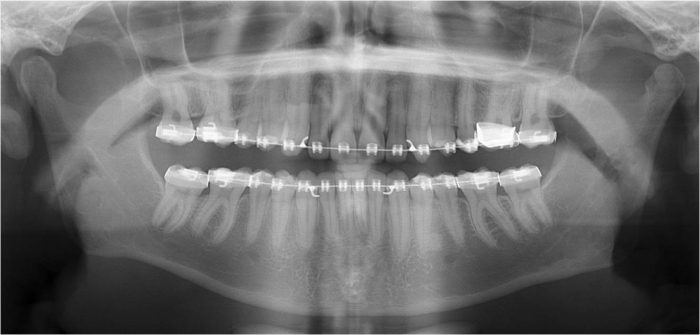

Raio x após a cirurgia